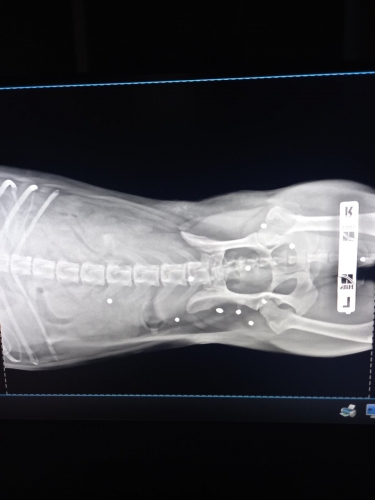

Оренбурженка связалась с волонтёрами приюта "Я - Живой". Удалось найти автомобиль, свозить животное в ветклинику. Как оказалось, её расстреляли из охотничьего ружья. В теле обнаружили 19 дробин. Не было практически ни одного живого места: повреждены голова, лапы, позвоночник, грудь, горло, живот, глаз. Врач отметил, что если бы стреляли с более близкого расстояния, то шансов выжить у бедной собаки не было бы...

Кроме того, собака была беременна. Щенков она потеряла. Белоснежку, как назвали пострадавшую собаку, ждут операция и длительное восстановление.

Вопрос об операции будет решаться после того, как ее состояние стабилизируется, ей нужно отогреться, так как два дня она пролежала в снегу, проколоть антибиотики, подождать сокращения матки и остановки кровотечения. Одно точно: левый глаз, залитый кровью, видеть не будет, дробь повредила его полностью, - отметили волонтеры.